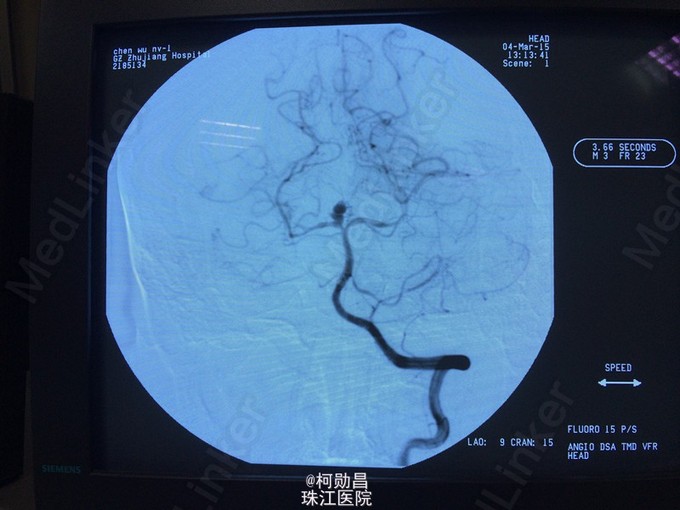

脑血管病常见病例(1)----------- 患者女,45岁,头痛,伴呕吐,CT提示蛛网膜下腔出血,DSA示大脑后动脉瘤,行介入栓塞治疗,术后恢复良好。